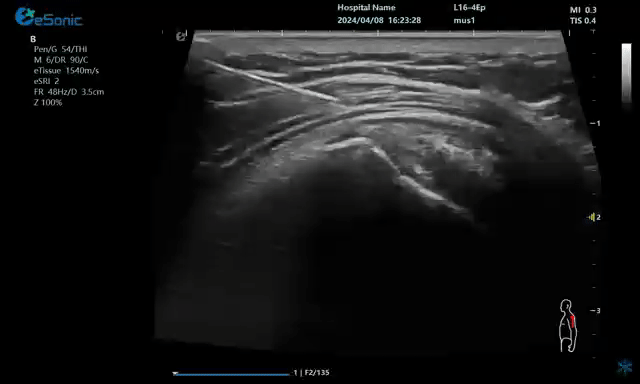

二、超声引导下注射准确性的临床验证及临床疗效研究

通过CT影像手段也验证了超声引导下注射的准确性。

超声引导下注射临床效果是否优于无超声引导下注射,部分研究显示了这方面的结果。